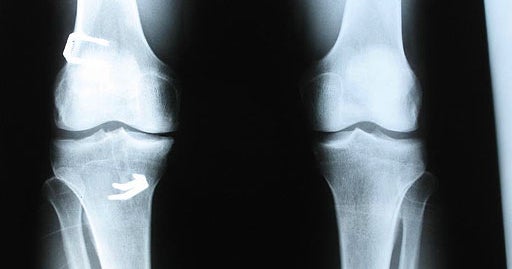

from www.evergreenpt.net